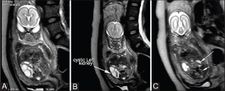

Oligohydramnios is a reduced amount of amniotic fluid. It occurs most often with rupture of the sac of membranes, also with placental insufficiency, developmental defects of the kidneys (agenesis, hypoplasia), developmental defects of the urinary tract, karyotype deviations and serious heart diseases Sonographically, oligohydramnios is defined under AFI 5. [1].